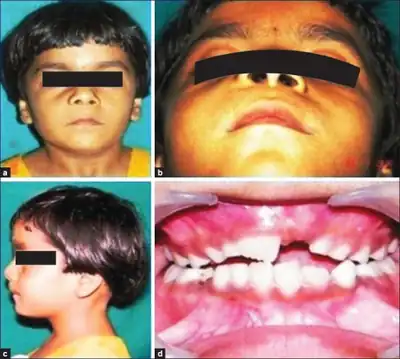

- Distinct faces: frontal and temporoparietal bossing, hypertelorism, and mandibular prognathism

- congenital malformations, such as cleft lip or palate, frontal bossing, eye anomaly (cataract, coloboma, microphthalmia, nystagmus).

- other skeletal abnormalities, such as Sprengel deformity, pectus deformity, polydactyly, syndactyly or hypertelorism.